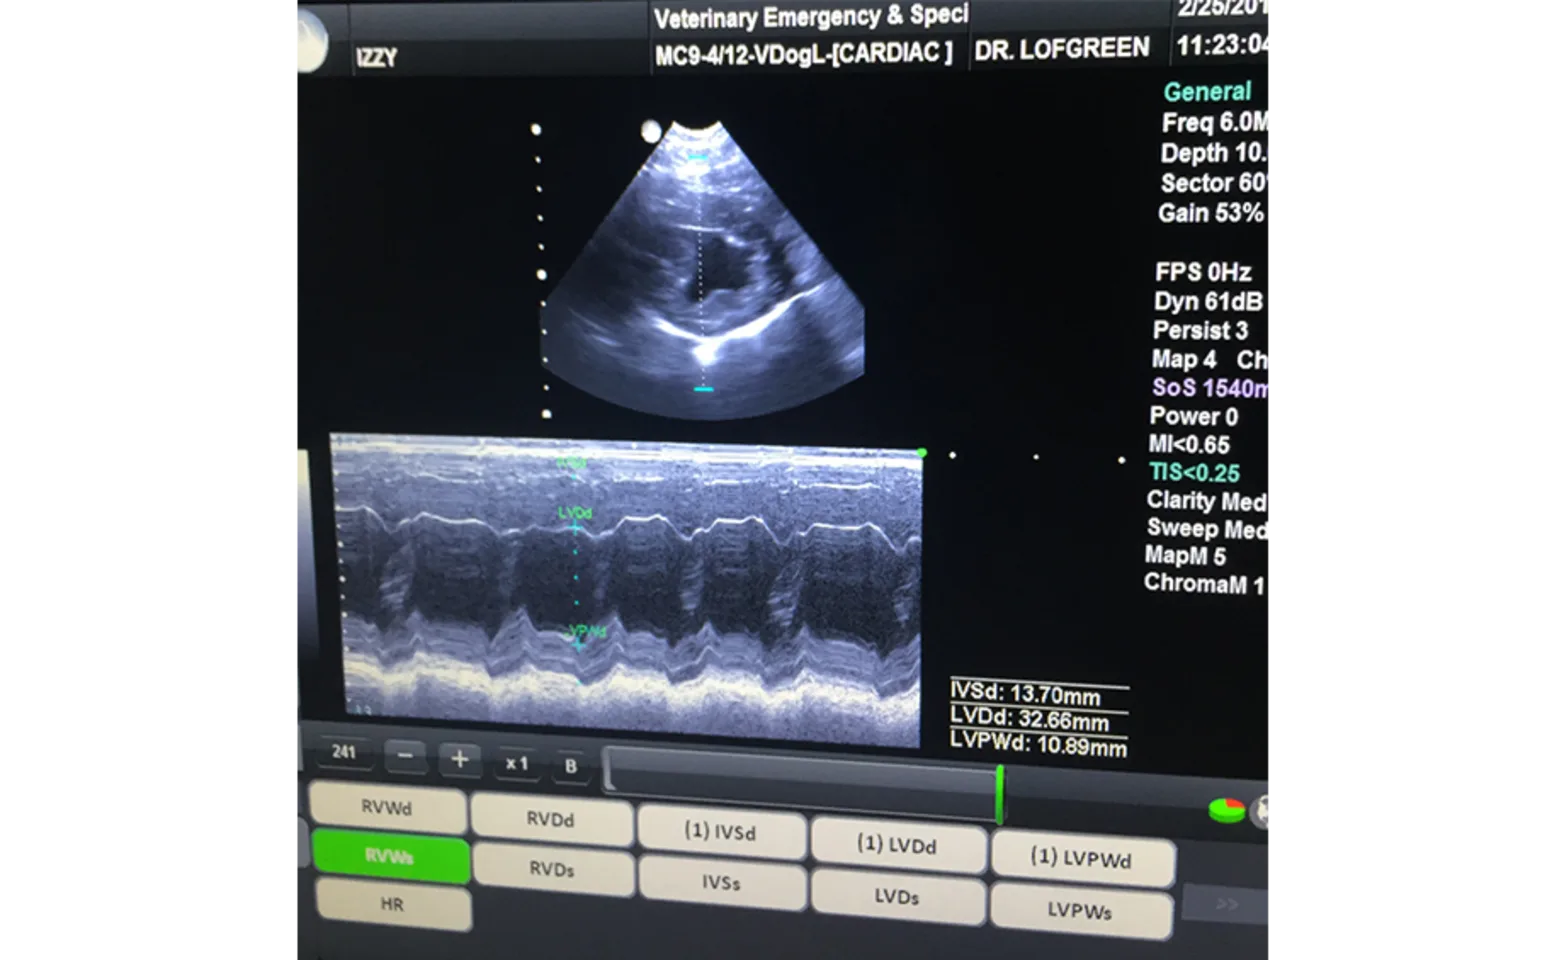

Echocardiography

This diagnostic imaging tool allows for a closer, incredibly detailed view of the heart’s function. Echocardiography allows specific measurements that lead to more precise diagnoses and more effective treatment plans. Echocardiography not only helps veterinarians diagnose heart disease, but also monitors the progress of ongoing treatment. An echocardiogram is used to evaluate heart disease, fluid around the heart or lungs, heart murmurs, or tumors.